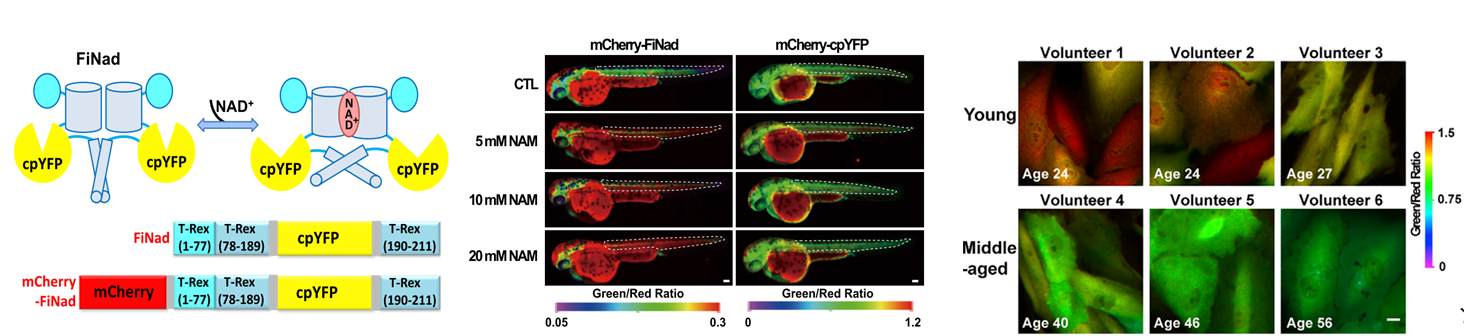

FiNad是一个高响应、高灵敏、大动态范围检测NAD+/AXP比率的遗传编码荧光探针,实现了细菌、酵母、哺乳动物细胞、斑马鱼和活体小水平NAD+成像。,可用于细胞信号转导、细胞代谢、衰老等领域研究(Developmental Cell, 2020)

乳酸是重要的能量燃料、合成砌块和信号分子,是具有多种关键作用的代谢“明星”,在生理和病理过程中发挥重要作用。乳酸代谢呈现剧烈的动态变化和复杂的空间分布,传统的生化方法难以实现活细胞和在体水平的动态追踪。我们发明了高特异、高响应、超灵敏的乳酸荧光探针FiLa,绘制了亚细胞乳酸代谢图谱,本研究意外发现线粒体基质内富集了高浓度乳酸,解决了该领域争议了几十年的重要科学问题。建立了基于FiLa探针的临床体液样本即时检测技术,发现尿液乳酸显著升高可能作为母系遗传性糖尿病伴耳聋(MIDD)疾病的潜在筛查标志物,为临床诊断提供了重要依据。(Cell Metabolism 2023, 35, 220; Nature Protocols 2023, in press)